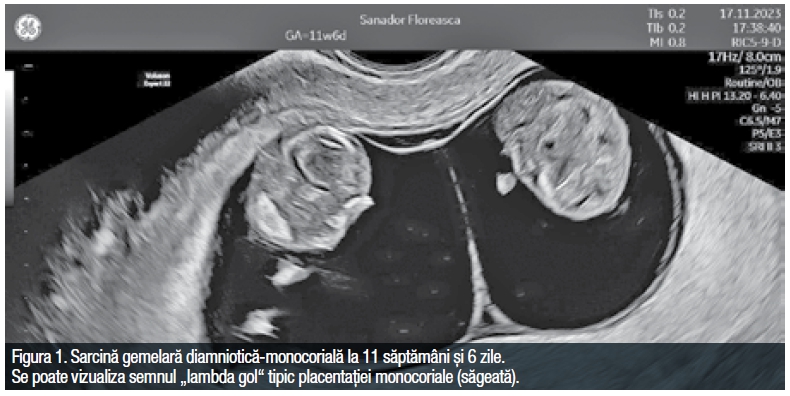

Determinarea antenatală a corio-amnionicității este esențială deoarece sarcinile monocoriale sunt grevate de mai multe complicații comparativ cu cele dicoriale. Din cauza anastomozelor vasculare placentare aceste sarcini prezintă și o serie de complicații particulare (TTTS, TRAP, TAPS, moartea fetală a unui dintre feți sau injuria neurologică a fătului supraviețuitor). Sarcinile monoamniotice sunt încă și mai complicate din cauza înnodării aproape universal întâlnite a celor două cordoane ombilicale și a anastomozelor vasculare extinse ce se asociază cu un risc ridicat de imbalanță acută a fluxului de sânge între cei doi feți.5 În consecință, stabilirea corio-amnionicității este recomandat a fi efectuată înainte de 13 săptămâni și 6 zile de sarcină pentru a evalua numărul maselor placentare, inserția membranei ce separă sacii gestaționali la nivelul placentei (semnul lambda „plin” sau twin peak și semnul lambda „gol” sau T) și grosimea acesteia (Figura 1).